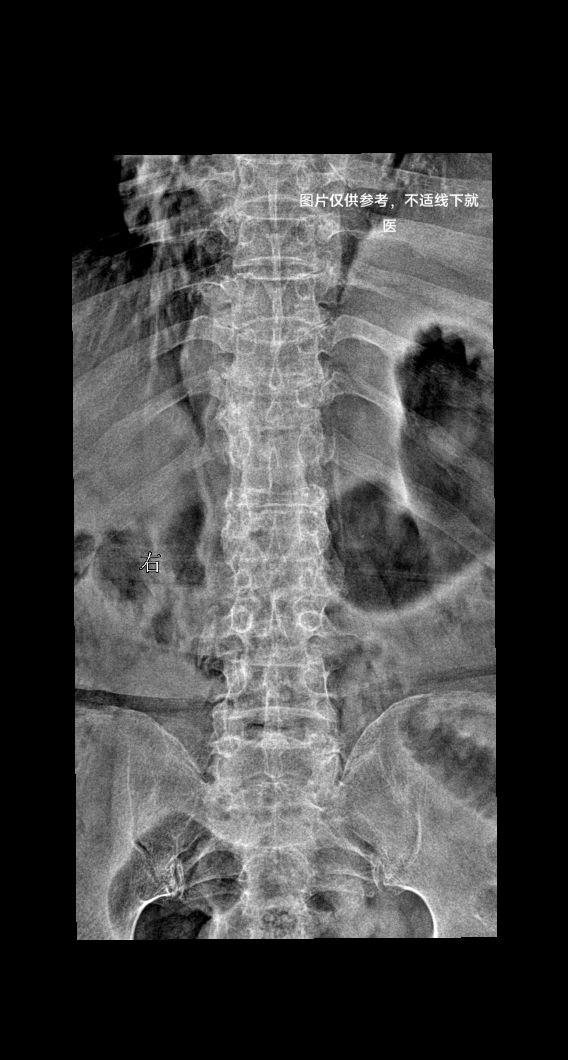

腰椎疼痛,下肢麻木酸疼

腰椎疼痛,滑脱几度?

腰部疼痛